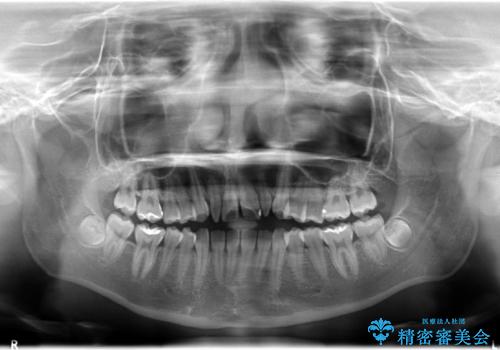

- ハーフリンガルシステムによる矯正治療を行いながら、スペースコントロールをみて前歯を仮歯へ

→矯正の終了をメドに仮歯をセラミックへ置き換える

上あごの2番目の歯は矮小歯といって、生まれつき小さい歯となる事がよくあります。

このような場合、矯正によりスペースを集め、本来あるべき形態にセラミックで修正することもできます。